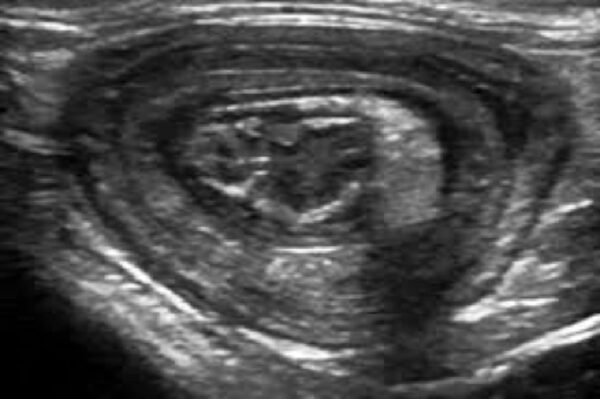

Tiger ist inzwischen ein 17-jähriger Europäisch-Kurzhaar-Kater. Letztes Jahr wurde er uns im Sommer wegen chronischer Magen-Darm-Beschwerden und Gewichtsverlusts vorgestellt. Trotz seines Alters scheuten seine Besitzer keine Kosten und Mühen. Im Ultraschall zeigten sich eine verdickte Darmwände, besonders die Muskelschicht war sehr dick (rote Markierung). Um der Ursache auf den Grund zu gehen, entnahmen wir Gewebeproben. Von dem Eingriff erholte sich Tiger sehr gut und die Wunden heilten ab.

Im Ultraschall ist deutlich zu sehen, dass die Darmwand nicht mehr verdickt und der Tumor unter Therapie derzeit unter Kontrolle ist.

Bei einer Ultraschalluntersuchung war ein mit Eiter gefüllter Hohlraum im Bereich der Gebärmutter darstellbar.

Eine Ultraschalluntersuchung bestätigte den Verdacht einer Gebärmutterentzündung.